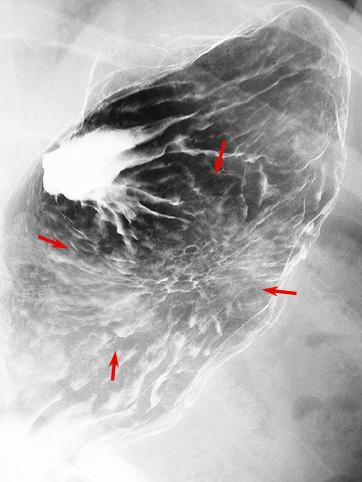

clasificación del pacienteTumor Epitelial Maligno/Adenocarcinoma

parte(separada por órganos)estómago(región)/cuerpo

método de exámenRayos X

clasificación ectoscópica de tumoresTipo 0(tipo superficial)/Tipo IIc(IIc)

diámetro mayor del tumor35 - 40

grado de penetraciónm